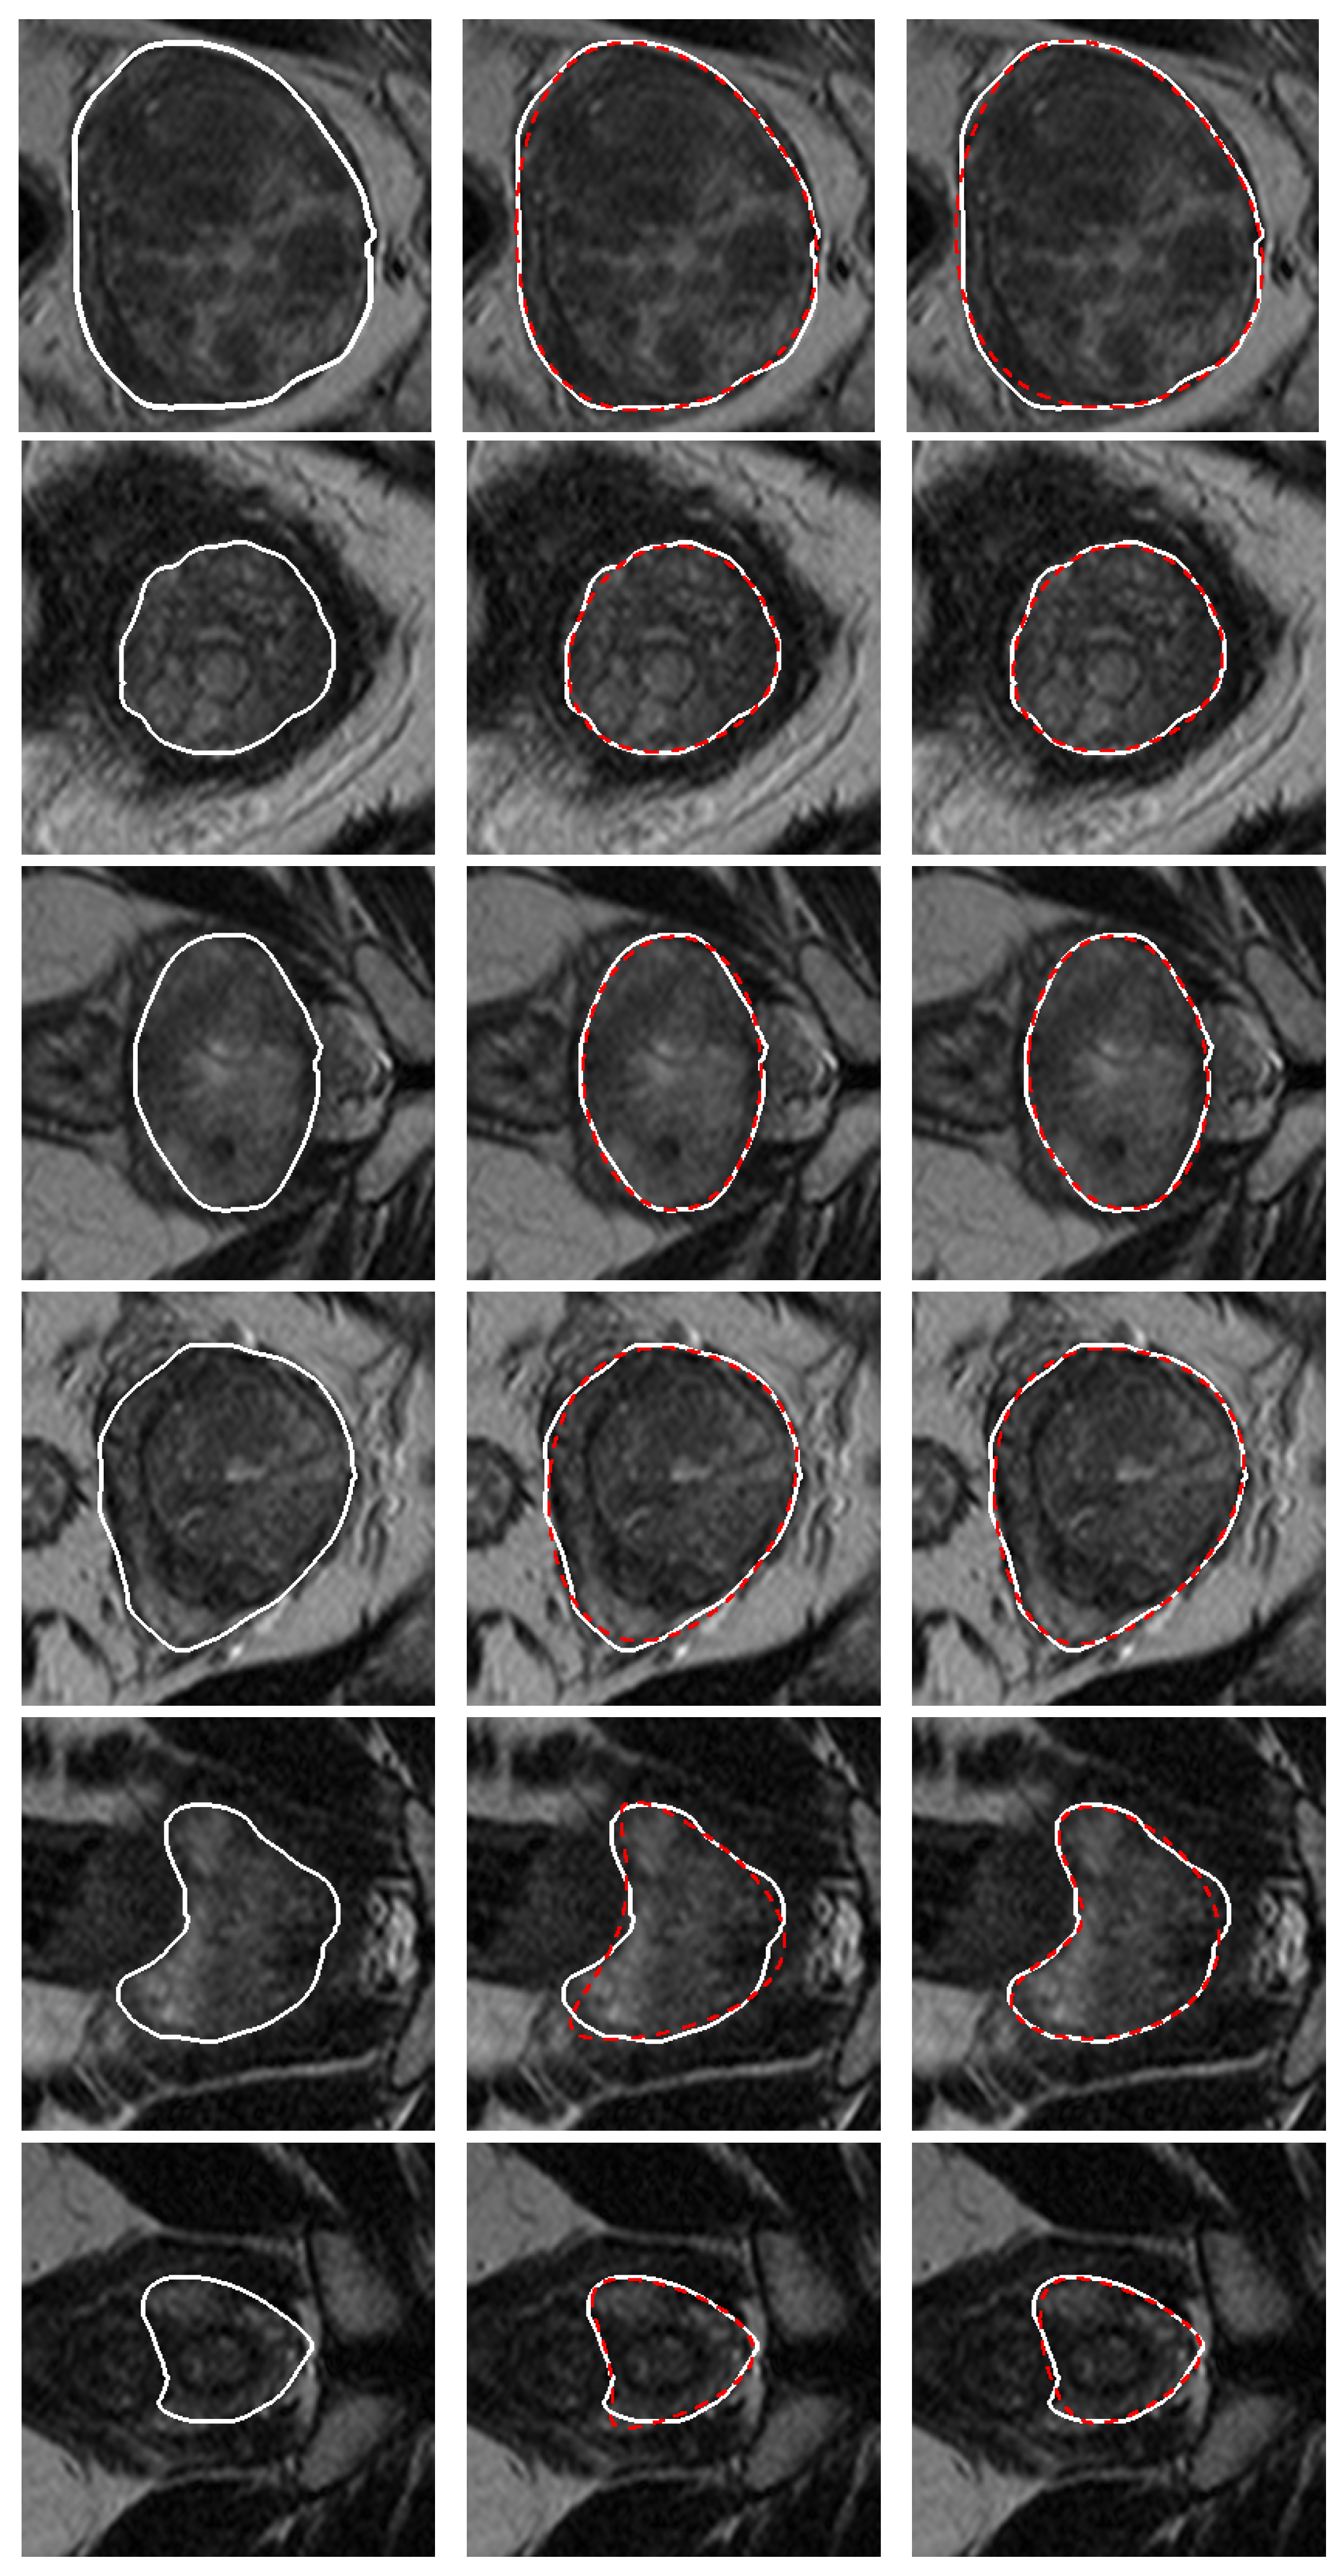

3. Validation of the Models

4. Results and Discussion

| Model | |||

|---|---|---|---|

| Best CS-CC | mm | mm | |

| CS | mm | mm | |

| CC | mm | mm | |

| Deformed superellipse | mm | mm |